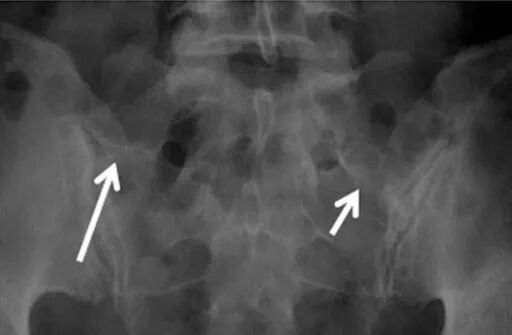

I型:横突发育不良增大,冠状位高度>19mm,尚未形成假性关节面

IIa型:单侧横突与骶骨形成假关节伴硬化,但未融合

IIb型:双侧横突与骶骨形成假关节伴硬化

(白箭指向假关节,但很难清晰显示)